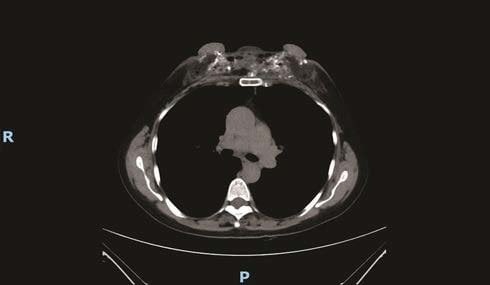

理想のオッパイを手に入れるため、胸に液状シリコン注射を何度もした女性の画像。

シリコン注入してから25年後に病院へやってきたそうです・・・。